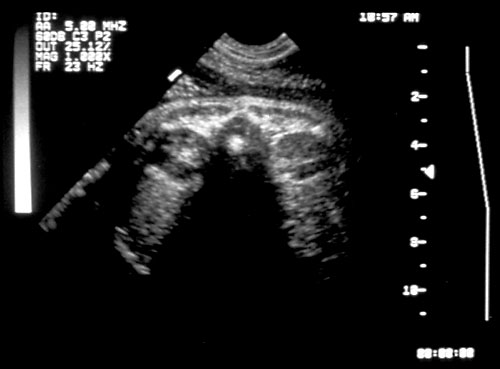

Normal fetal bladder at 18 weeks (left, at arrow). Lovely picture of both uterine arteries around normal bladder (right). This color flow picture documents the presence of the 3 vessel cord with the demonstration of the two uterine arteries coursing around the bladder. - Spine (need two perpendicular views)